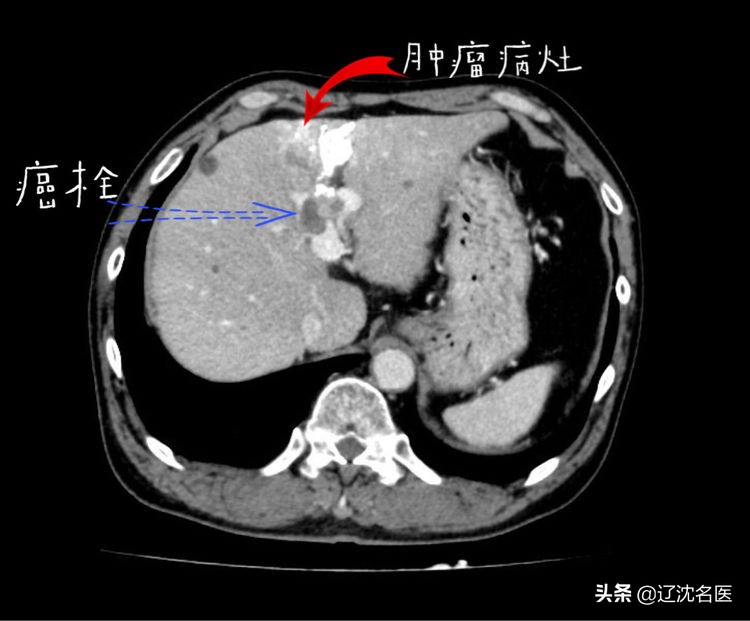

2019年4月,患者就诊于外院,经CT检查,考虑肝细胞癌合并门脉左支癌栓形成、腹腔淋巴结转移。

2019年12月行肝脏影像学检查提示门脉栓子形成,经系统检查诊断:

患者术前CT